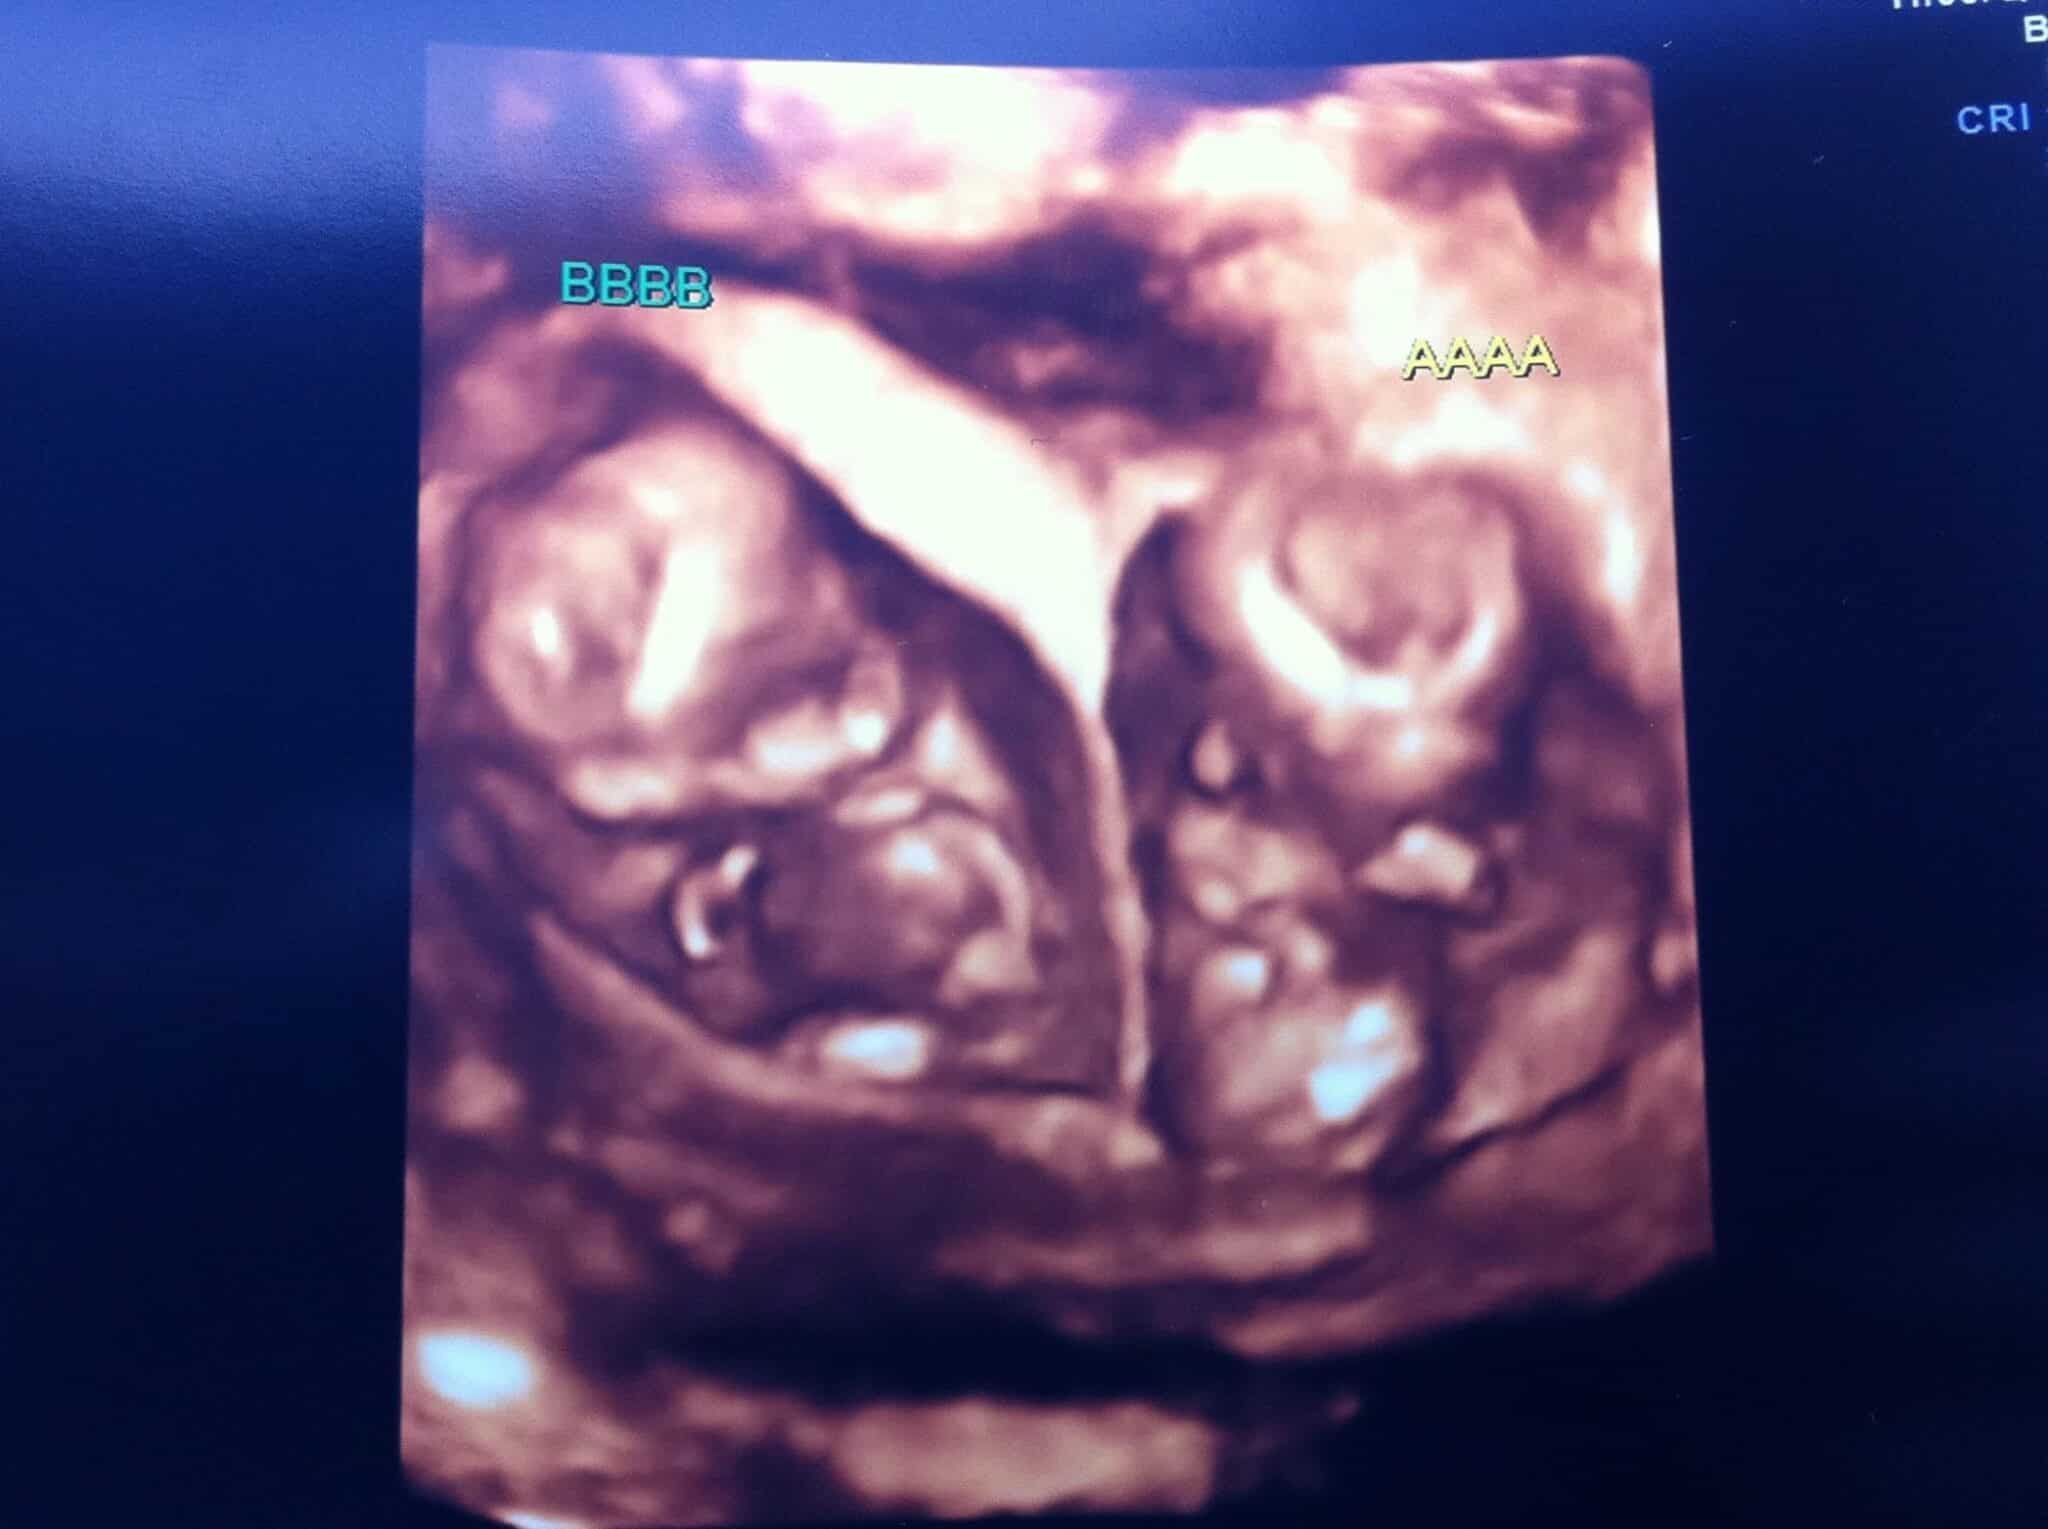

Ultrasound Photos at 12 Weeks Pregnant With Twins